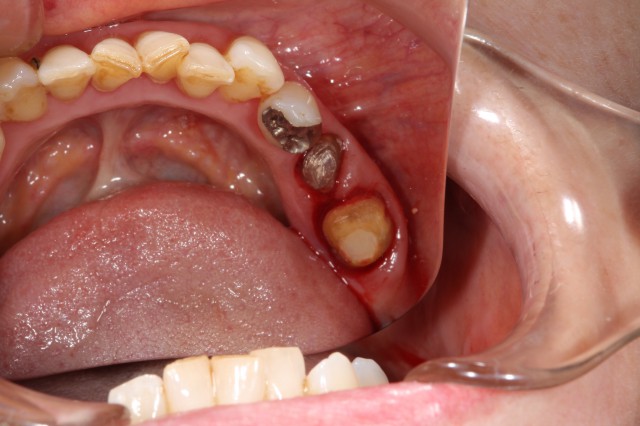

施術中